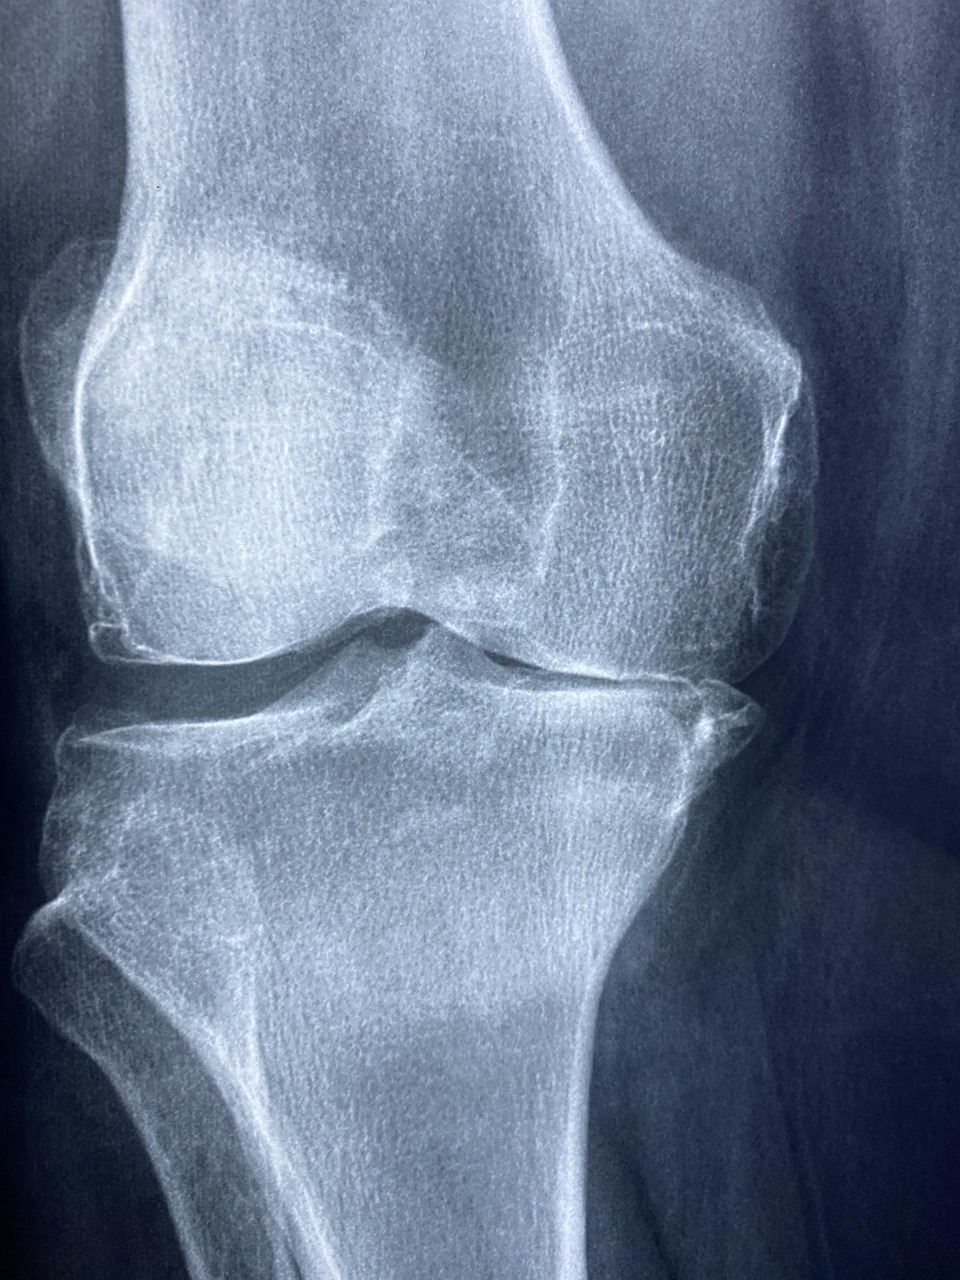

무릎관절염 증상, 어떻게 나타날까?

무릎관절염은 노화, 과체중, 반복적인 무릎 사용 등으로 인해 무릎 연골이 점차 손상되면서 발생하는 질환입니다. 초기에는 단순한 무릎 통증으로 시작되지만, 점차 증상이 심해지면 계단을 오르내리거나 오래 걷는 것조차 힘들어질 수 있습니다. 가장 흔한 무릎관절염 증상은 아침에 일어났을 때 무릎이 뻣뻣하게 굳는 관절 강직, 활동 시 심해지는 통증, 그리고 계단을 내려올 때 느껴지는 무릎 압박감입니다.

관절염이 진행되면 무릎이 붓거나 열감이 동반되고, 무릎이 점차 휘어지는 변형도 나타납니다. 심한 경우에는 다리를 펴고 걷기 어려워지고, 관절에서 소리가 나는 현상(마찰음)도 자주 발생합니다. 무릎관절염은 단순한 불편함을 넘어서 삶의 질을 크게 떨어뜨리기 때문에 조기 발견과 관리가 무엇보다 중요합니다.

무릎관절염 치료와 관리의 균형

무릎관절염은 완치보다는 관리가 중요한 질환입니다. 약물치료나 주사치료로 통증을 줄이는 것도 도움이 되지만, 장기적인 관점에서는 생활습관 관리와 운동이 가장 효과적입니다. 증상이 심한 경우에는 인공관절 수술 같은 외과적 치료가 필요할 수 있지만, 대부분의 환자는 올바른 운동법과 체중 관리만으로도 증상 완화와 진행 억제가 가능합니다.